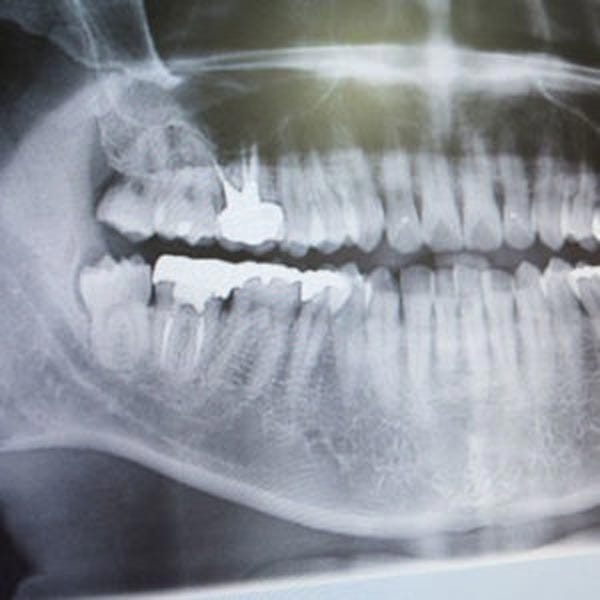

Implants and Bone Loss

A tooth’s root is important to help maintain bone health. When the root is missing or removed, such as when a tooth is extracted, the bone in that area is reabsorbed by the body and can cause a number of oral issues. Dental implants take the place of the missing root, stimulating the jawbone, and preventing this deterioration.

The bone loss progression models pictured here shows, in the left image, a normal complement of teeth and natural lower jaw bone mass and height.

Dr. Nazarian uses specialized bone grafting products and implant placement procedures to replace lost bone and to provide sensible anchoring methods for patients who prefer removable prosthetics.

For those patients who have been told they are not a candidate for traditional dental implant treatments, Dr. Nazarian can use subperiosteal devices to recreate an entire ridge of new bone that’s necessary for attaching prosthetic teeth.